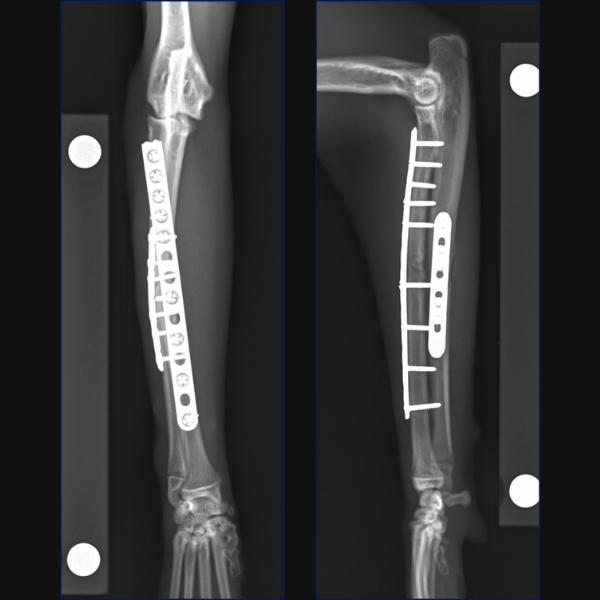

Separate minimally invasive approaches were made for the radial and ulnar fractures to facilitate placement of a 10-hole 1.5/2.0 LCP cranially on the radius with 3 screws proximally and 3 distally. A 7-hole 1.5/2.0 LCP was then placed laterally on the ulna through proximal and distal stab incisions. Lastly, the ulnar styloid fracture was stabilized minimally invasively through a stab incision using a 1.2mm K-wire.